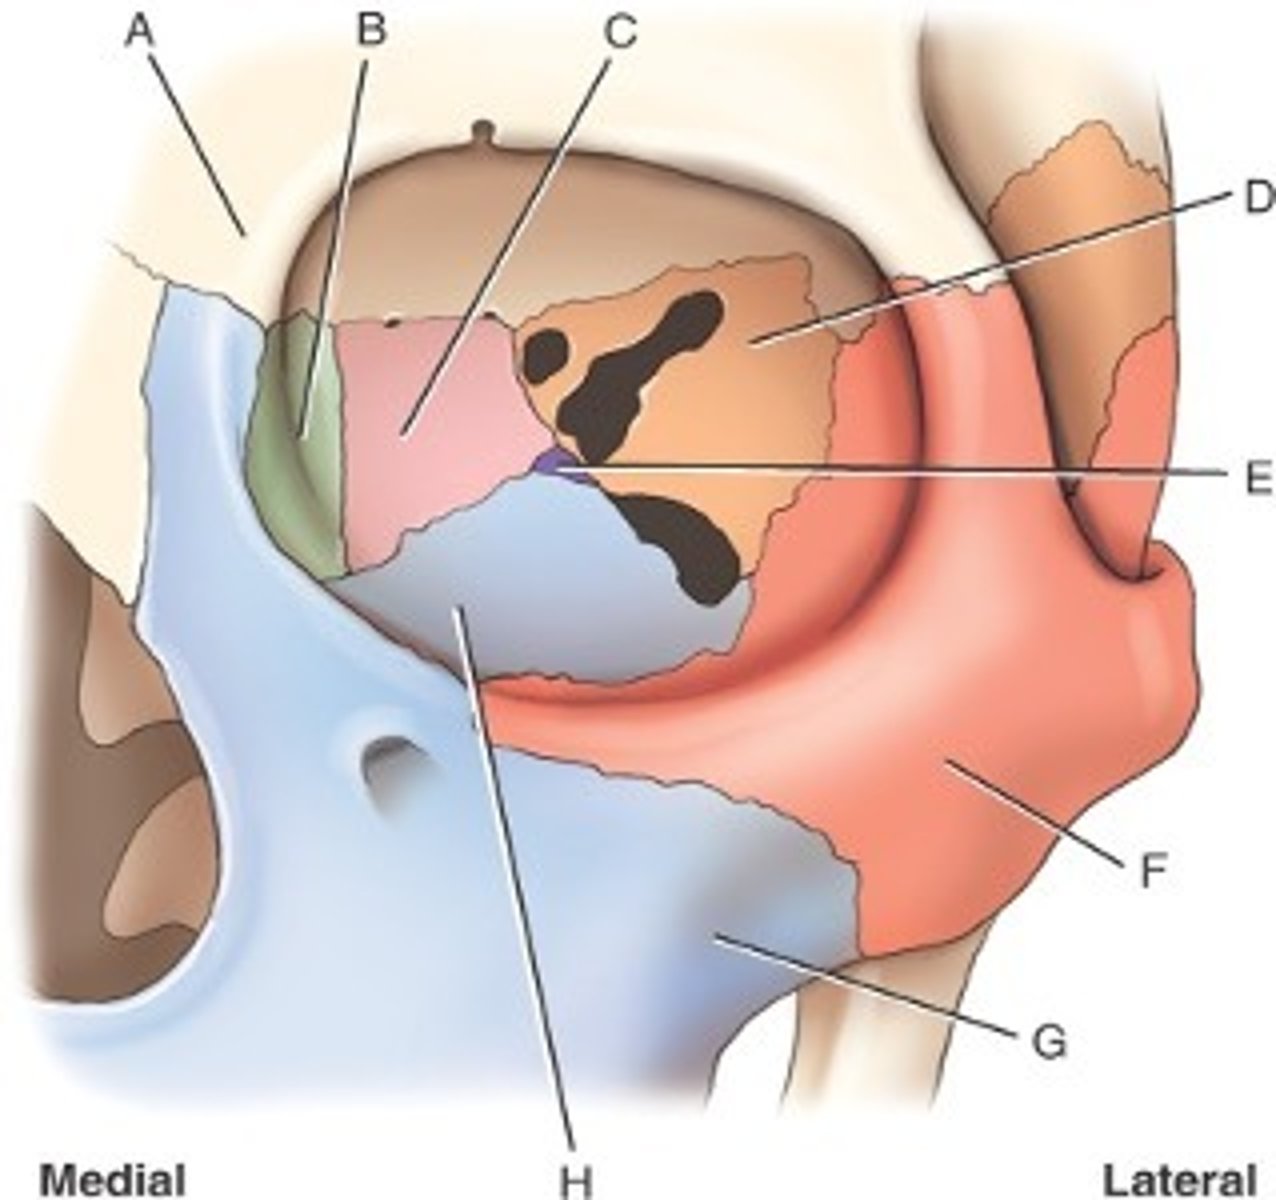

What is B

frontal bone

What is A

ethmoid

What is C

sphenoid

what is D

Palatine

What is E

Zygoma

What is F

Maxilla

What is G and H

optic foramen in orbit

sphenoid strut